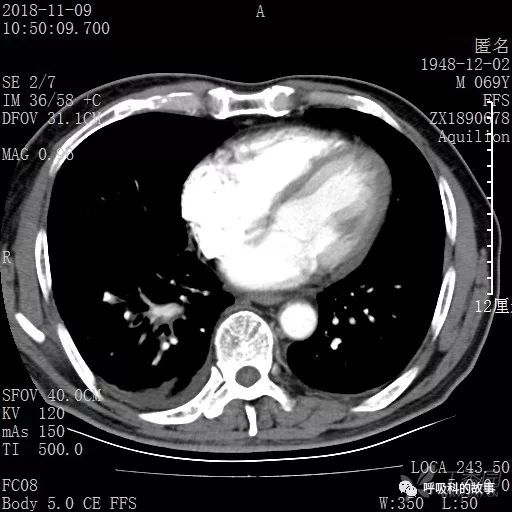

胸部增强CT示右肺门占位伴远端阻塞性肺炎,纵膈、右肺门、右侧颈根部、右侧腋下及肝门部肿大淋巴结。两侧胸腔少量积液。

肺窗CT